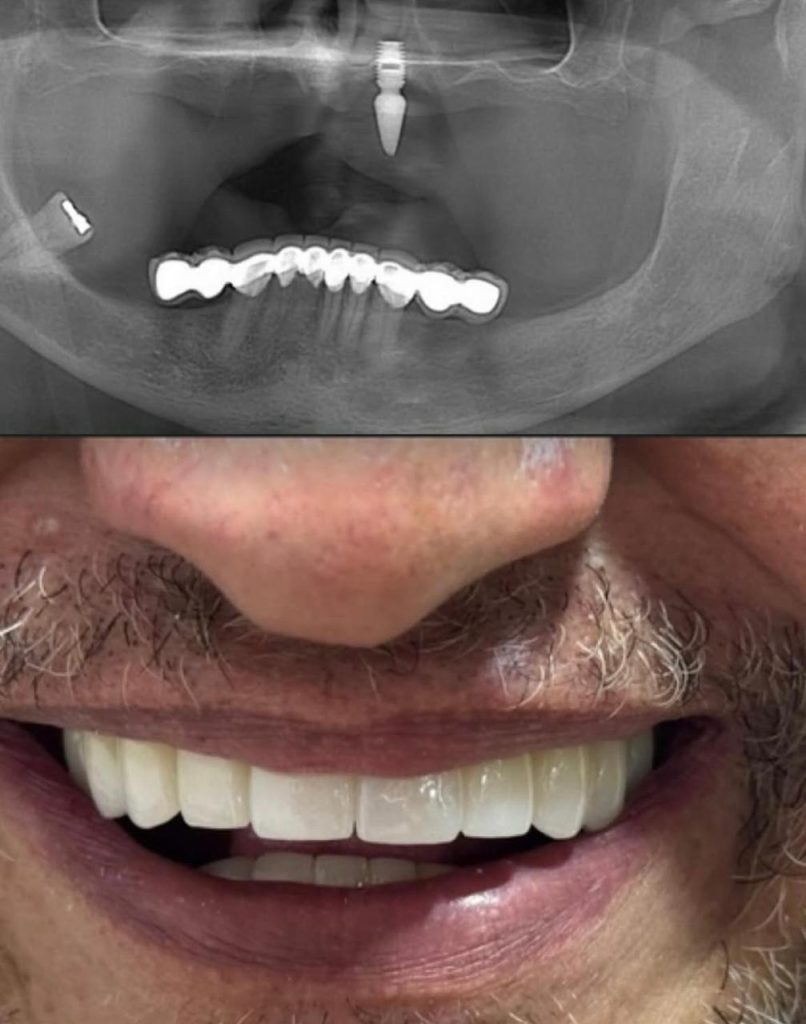

Dental implant rejection refers to the body’s inability to properly integrate the titanium implant into the jawbone. This can happen shortly after surgery or even months later. While the success rate is over 90%, some cases fail due to biological or procedural factors.

This is when the implant doesn’t bond with the jawbone. Causes may include insufficient bone density, poor surgical technique, early implant movement, or systemic diseases like osteoporosis.Preexisting medical conditions: